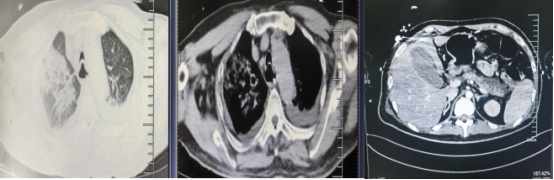

2025年12月,25岁的薛先生因持续13天的剧烈腹痛被紧急送到海医一附院。此前,他已被诊断为糖尿病酮症酸中毒和急性胰腺炎,血糖值一度飙升至致命的47.93mmol/L,并出现气促、恶心、精神恍惚乃至休克症状,病情极其危重。

薛先生检查结果图。院方供图

年仅25岁,既往有痛风、糖尿病却未规律治疗的他,入院时已面临双肺严重感染、腹腔积液、呼吸窘迫,多器官功能衰竭风险极高的局面,被直接送入重症医学科(ICU)抢救。

经过17个日夜的全力救治,薛先生的生命体征逐渐平稳,神志转清,成功脱离了呼吸机支持,血氧饱和度稳定在98%以上。后续复查显示,其胰腺周围渗出明显吸收,肺部感染情况大幅好转,腹腔积液显著减少。